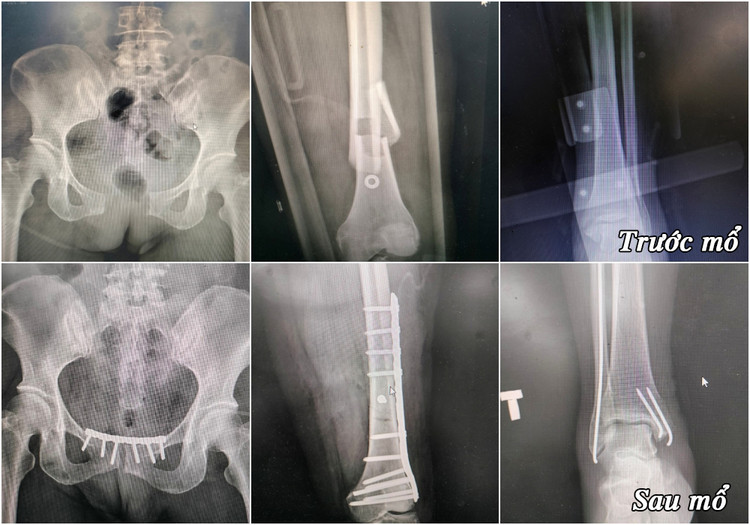

Tại đây, kíp bác sĩ Bệnh viện Đa khoa tỉnh Quảng Ninh và TTYT huyện Vân Đồn phối hợp truyền máu hồi sức, mổ cấp cứu xử trí ban đầu cho 3 nạn nhân. Hội chẩn đánh giá bệnh nhân B. tiên lượng nặng nề nhất với chẩn đoán sốc đa chấn thương, chấn thương khung chậu toác khớp mu, gãy hở phức tạp xương đùi phải, gãy đầu dưới 2 xương cẳng chân phải.

3 phẫu thuật kết hợp xương cho bệnh nhân B. được kíp phẫu thuật khoa Chấn thương chỉnh hình thực hiện trong 1 cuộc mổ.

Kíp mổ khoa Chấn thương chỉnh hình do bác sĩ Trần Đình Duy phụ trách phối hợp với bác sĩ CKI Phạm Trung Đức, khoa Gây mê hồi sức thực hiện phẫu thuật. Trong một cuộc mổ, phẫu thuật viên đã đồng thời thực hiện 3 phẫu thuật để xử trí các đa chấn thương phức tạp. Kíp mổ làm sạch ổ gãy phức tạp xương đùi phải, đặt lại ổ gãy về vị trí và cố định lại bằng nẹp vít.

| Hình ảnh xương gãy của bệnh nhân trước và sau mổ |

Để xử trí vùng khớp mu toác rộng, phẫu thuật viên khéo léo ép đặt lại khớp và cố định bằng nẹp vít, sau đó khâu phục hồi vết mổ theo giải phẫu. Với tổn thương gãy kín đầu dưới 2 xương cẳng chân phải, các bác sĩ đã thực hiện phẫu thuật kết hợp xương ít xâm lấn với sự hỗ trợ của máy C-arm chụp X-quang di động, giúp người bệnh giảm bớt đau đớn khi phải trải qua nhiều phẫu thuật cùng lúc.